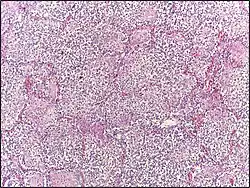

Micrograph of lobar pneumonia, H&E stain.

Lobar pneumonia usually has an acute progression. Classically, the disease has four stages:[1]

• Congestion in the first 24 hours: This stage is characterized histologically by vascular engorgement, intra-alveolar fluid, and small numbers of neutrophils, often numerous bacteria. Grossly, the lung is heavy and hyperemic.

• Red hepatization or consolidation: Vascular congestion persists, with extravasation of red blood cells into alveolar spaces, along with increased numbers of neutrophils and fibrin. The filling of air spaces by the exudate leads to a gross appearance of solidification, or consolidation, of the alveolar parenchyma. This appearance has been likened to that of the liver, hence the term "hepatization".

• Grey hepatization: Red blood cells disintegrate, with the persistence of neutrophils and fibrin. The alveoli still appear consolidated, but grossly the color is paler and the cut surface is drier. This is when death typically occurs in severe cases.

• Resolution (complete recovery): The exudate is digested by enzymatic activity, and cleared by macrophages or by cough mechanism. Enzymes produced by neutrophils will liquefy exudates, and this will either be coughed up in sputum or drained via lymph.